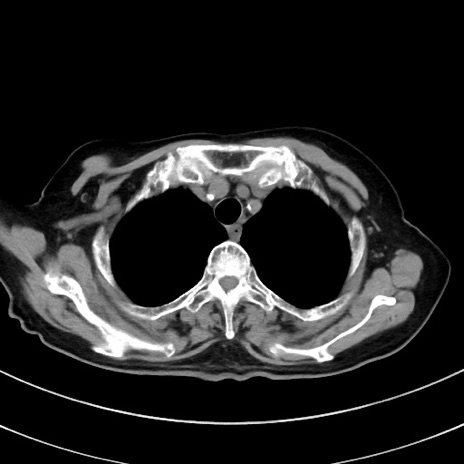

症例33(横断像)

【症例】70歳代 女性

【主訴】心窩部痛

【現病歴】延髄病変の精査・加療にて神経内科入院中。本日より心窩部痛あり。

【既往歴】虫垂炎

【身体所見】右下腹部を中心に圧痛と反跳痛あり。

【データ】WBC 10900、CRP 0.02